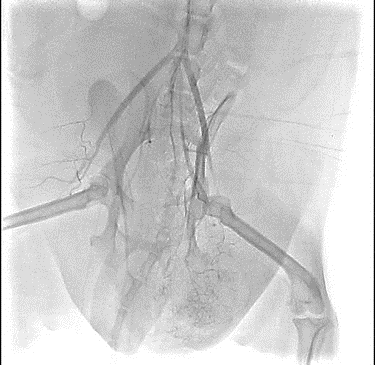

【実施症例】腰下リンパ節に転移した血管肉腫に対する動注療法

ゴールデン・レトリーバー、11歳、雄。

腰下リンパ節に転移した血管肉腫。

腫瘍の頭側の腹大動脈にリザーバーを設置し、抗がん剤の投与を行った。腫瘍は1/3以下に縮小が認められた。

血管肉腫が転移した腰下リンパ節

腫瘍陰影(DSA画像)

実施前

実施後